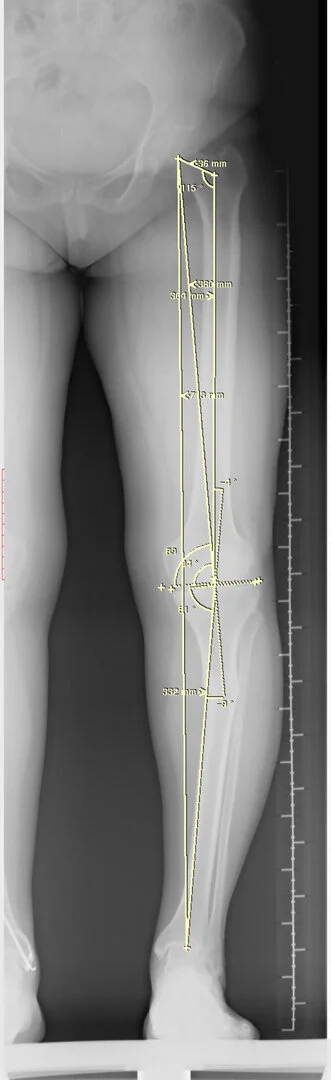

Diz Çevresi Osteotomileri (Yüksek Tibial Osteotomi (YTO) ve Distal Femoral Osteotomi)

Normal bir kişide diz eklemi hafif içe doğru eğimlidir. Bunu genu varus olarak adlandırmaktayız. Bazen bu varus açısı fazla olduğu zaman diz ekleminin iç tarafına anormal yük binerek erken dönemde kireçlenme ortaya çıkmaktadır. Özellikle genç hastalarda bu durumun düzeltilmesi gereklidir. Aksi takdirde daha erken dönemde diz ekleminde problemler yaşamaya başlarlar.

Bu ameliyat öncesi bir deformite analizi yapılıp hangi kemikte, normalden ne kadar sapma olduğu tespit edilir. Daha sonra bu kemiğe yine ostetomi yapılarak bu anormal sapma düzeltilir.  Bu düzeltme plak-vida veya intramedüller çivi ile akut olarak düzeltilebileceği gibi bilgisayar destekli sirküler eksternal fiksatör ile tedrici olarak ta yapılabilir. Hangi yöntemin hangi hasta için uygun olacağına hasta özelinde karar veriyoruz, ne tür cerrahi tedavi olması gerektiğini danışabilirsiniz.

Görüntüleri büyütmek için üzerine tıklayınız.